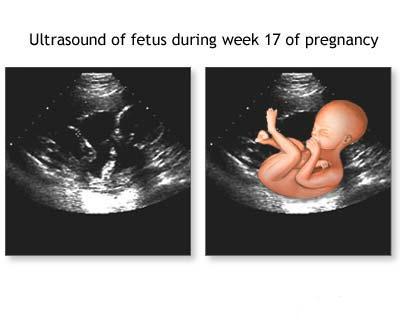

Poze Medicale Aplicatia Ecografiei In Obstetrica

Ecografie 4d Sarcina 20 Saptamani 4d Cabinet Ginecologie Ecografie Rm Valcea

Ecografia In Sarcina Afla Raspunsurile La Cele Mai Frecvente Intrebari In Legatura Cu Acest Tip De Analiza

Ecografie 3d 4d Blogul Dr Romeo Stanescu Medic Primar Ginecolog Doctor In Medicina Pagină 3